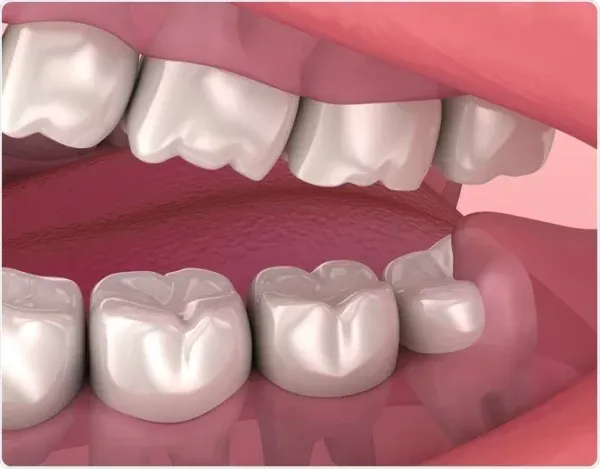

Solution : Crown

Solution : Composite Filling, Crown, Porcelain Veneer